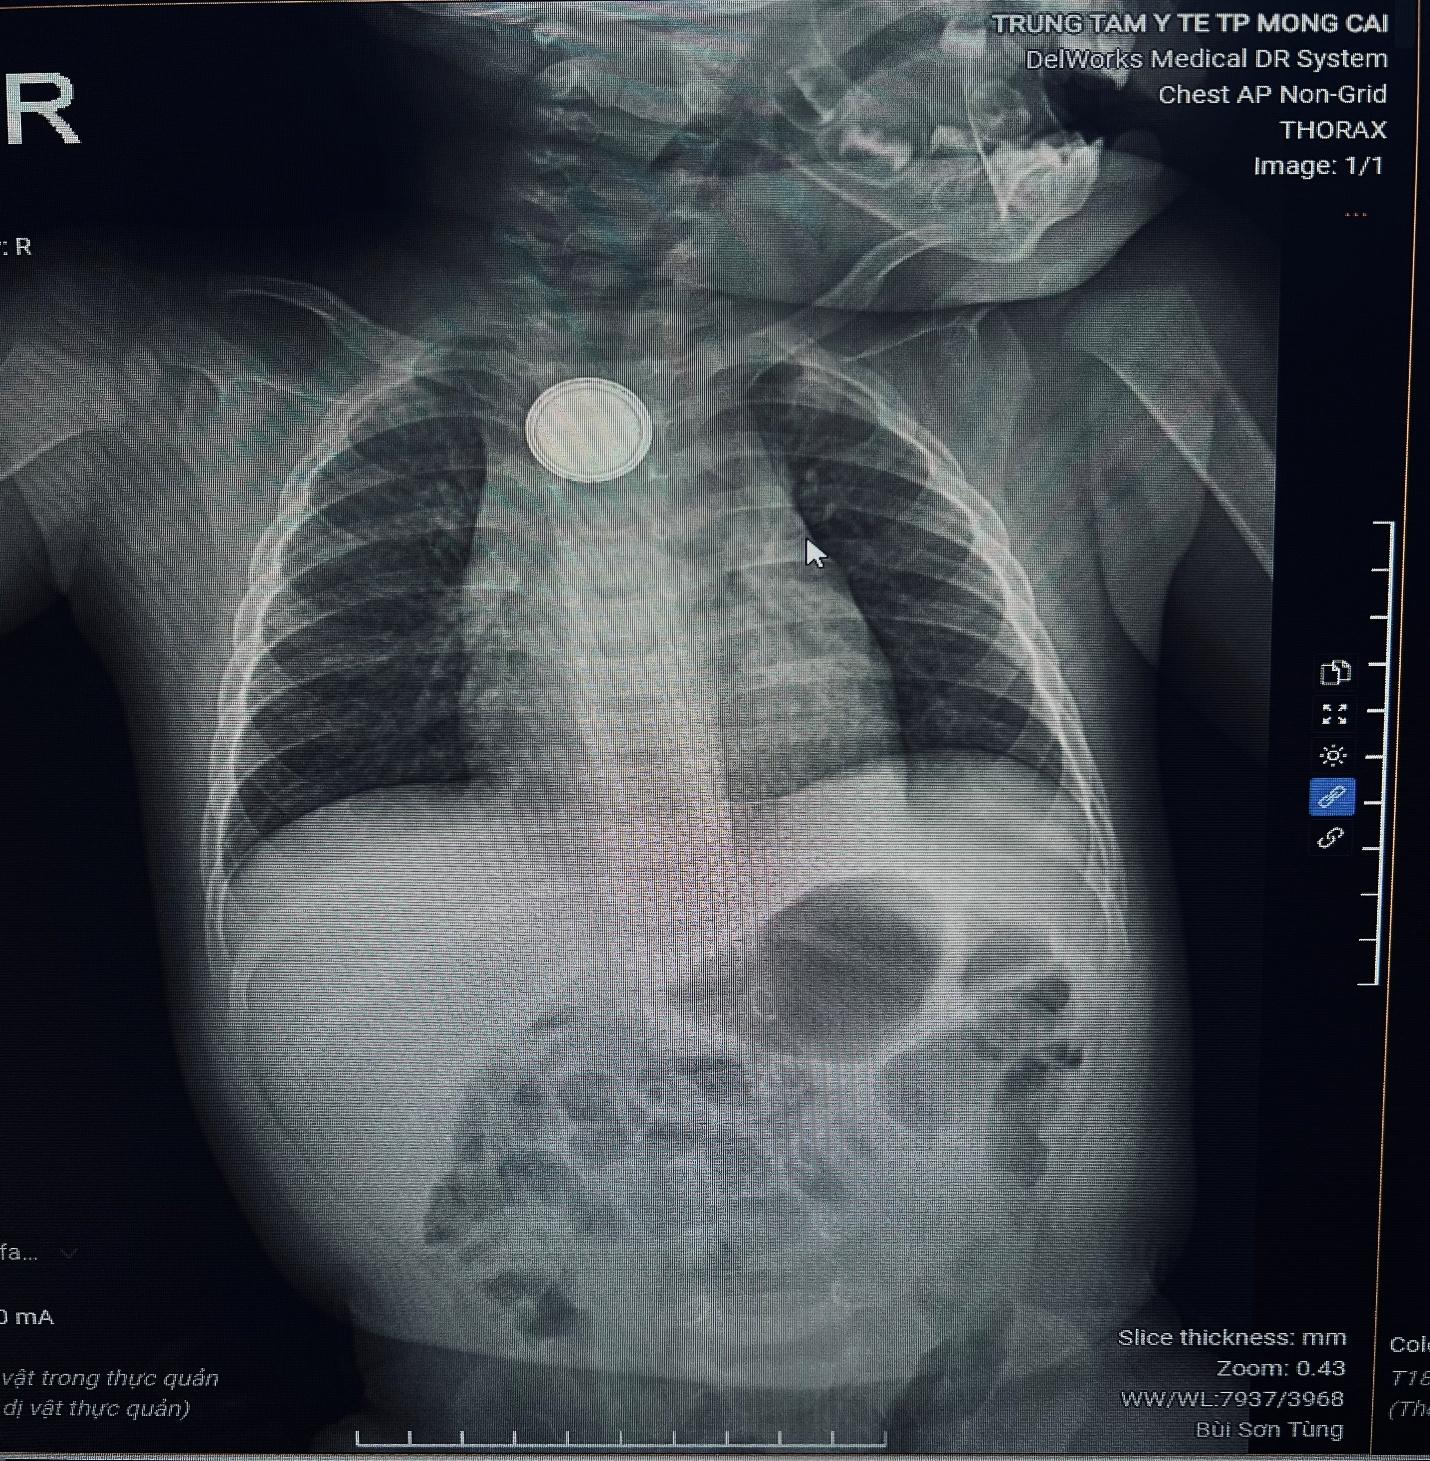

Vừa qua, Trung tâm Y tế thành phố Móng Cái tiếp nhận một trường hợp bệnh nhi B.M.K 11 tháng tuổi nhập viện trong tình trạng nôn nhiều, quấy khóc. Qua thăm khám và chụp X-quang, bác sĩ phát hiện một dị vật hình tròn kim loại – mắc kẹt tại thực quản.

(Hình ảnh: chụp Xquang phát hiện dị vật thực quản )

Bệnh nhi được chỉ định nội soi cấp cứu và phát hiện dị vật là một viên pin cúc áo. Dị vật được lấy ra thành công, tuy nhiên niêm mạc thực quản đã bị do tác động ăn mòn của pin. Hiện bệnh nhi đang được điều trị tích cực và theo dõi biến chứng do dị vật gây nên.